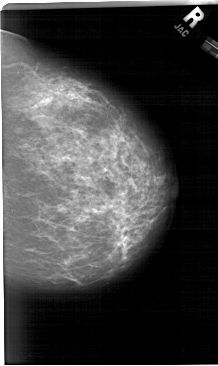

A_1284_1.RIGHT_MLO

RIGHT_CC LINES 6571 PIXELS_PER_LINE 3916 BITS_PER_PIXEL 12 RESOLUTION 43.5 NON_OVERLAY

RIGHT_MLO LINES 6751 PIXELS_PER_LINE 4081 BITS_PER_PIXEL 12 RESOLUTION 43.5 NON_OVERLAY